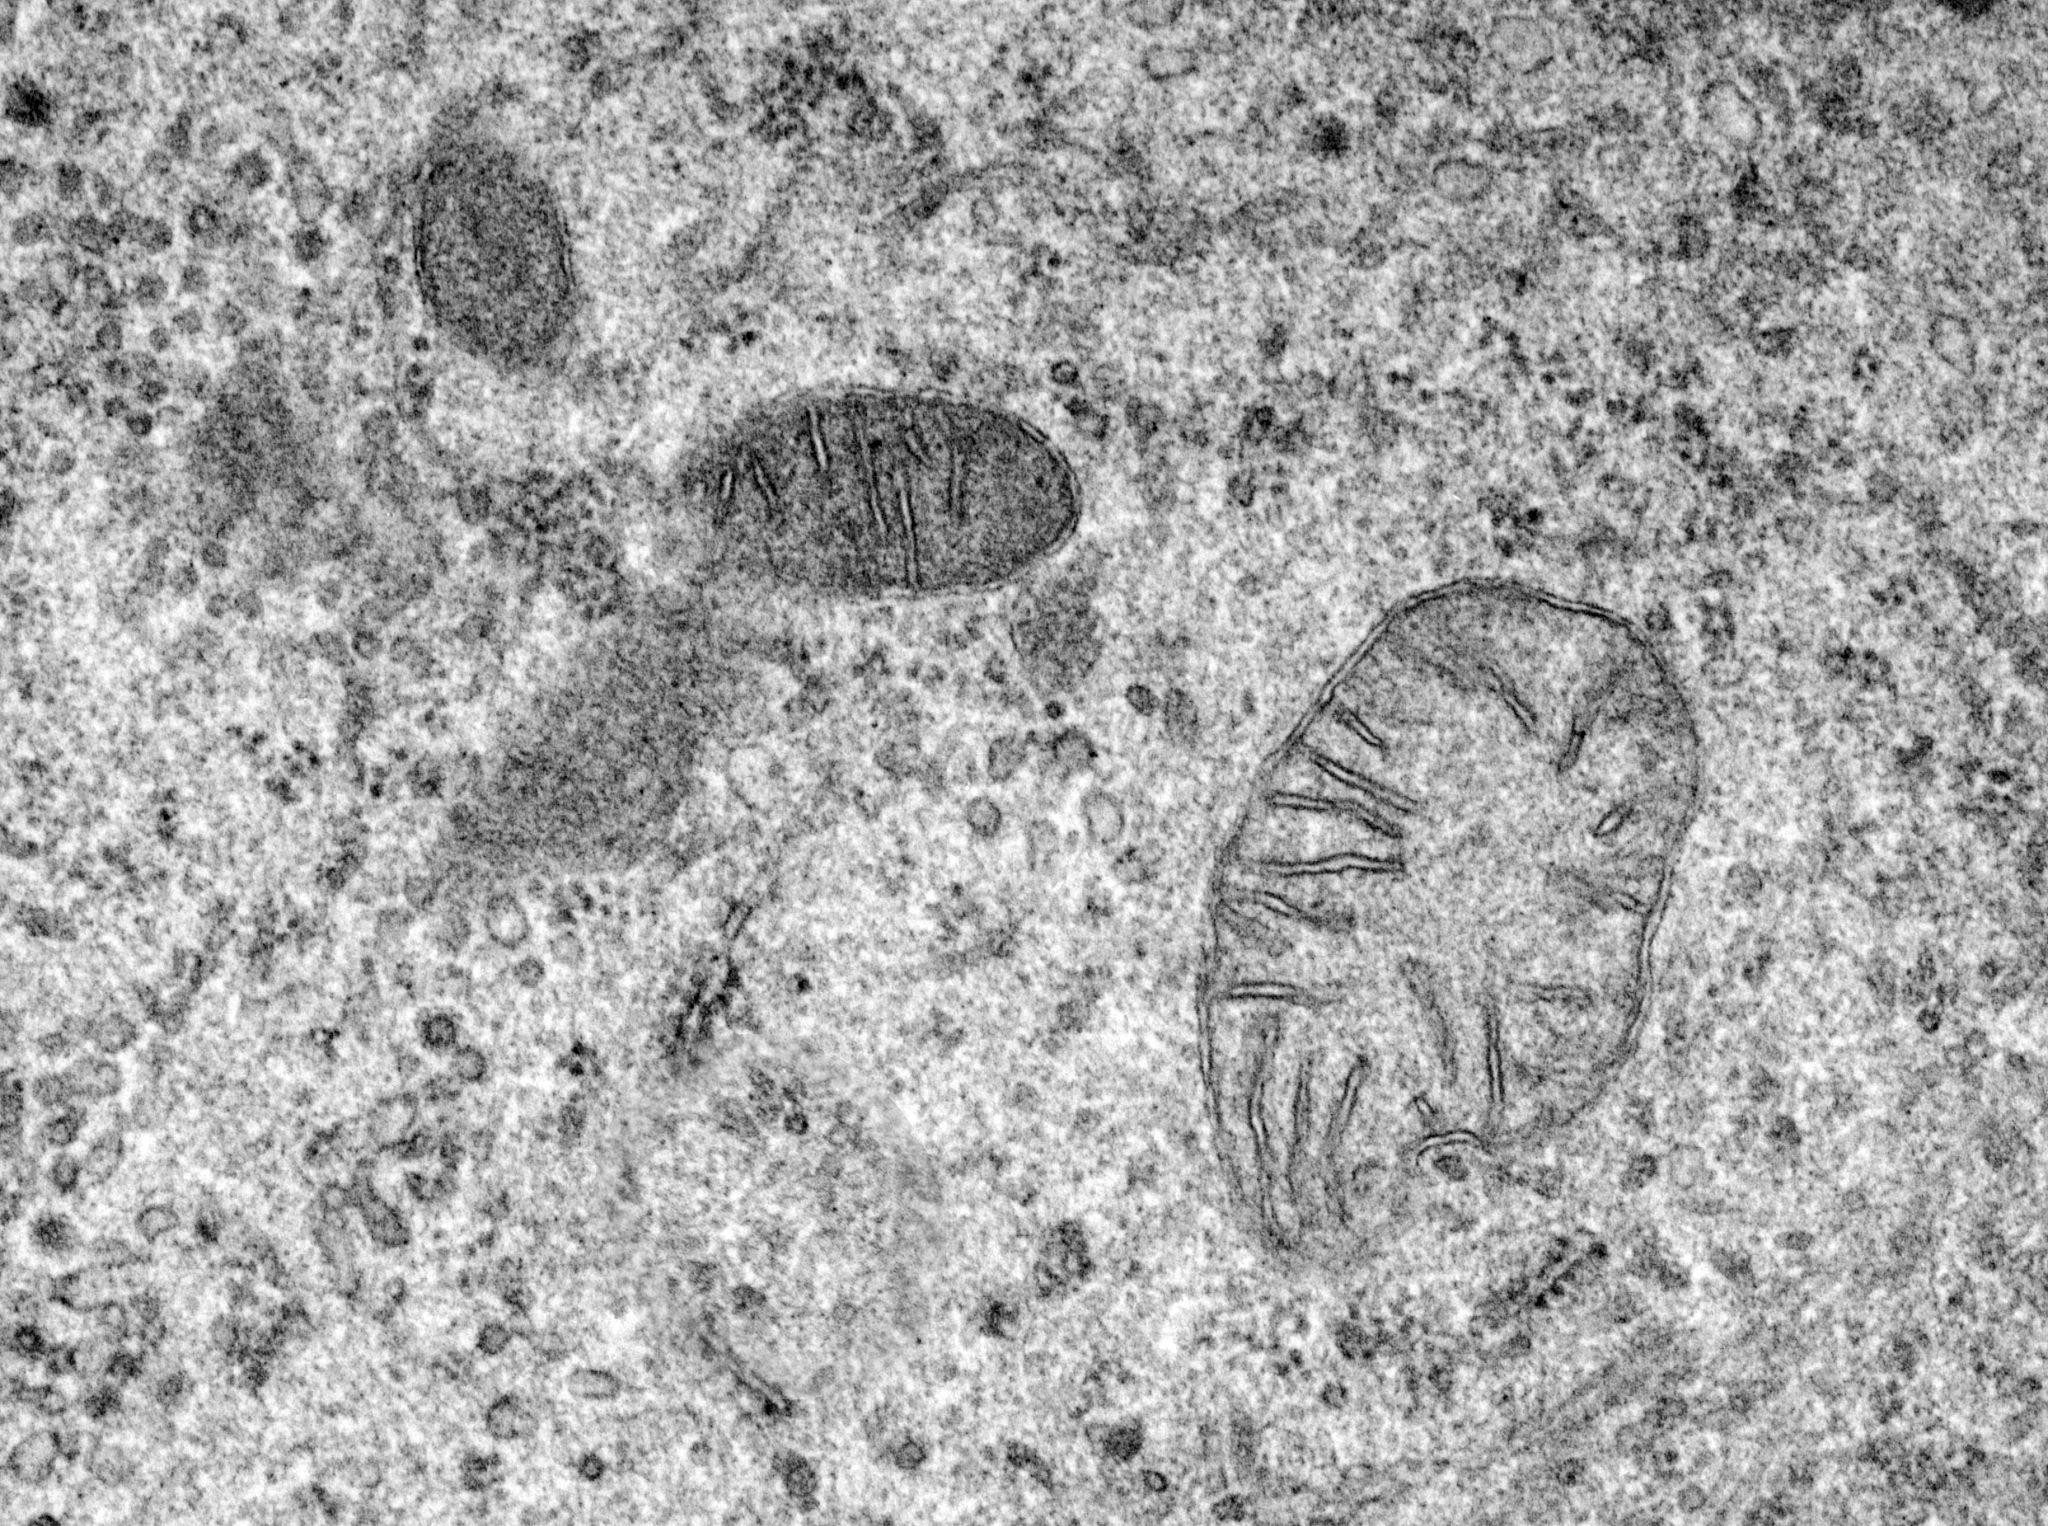

A mitokondriumok a sejtek „erőművei”. Olyan sejtszervecskék, amelyek a tápanyagokból energiát állítanak elő a sejt számára.

- kettős membránjuk van

- saját DNS-ük van (mitokondriális DNS)

- önállóan képesek osztódni

Ez azért érdekes, mert az egyik tudományos elmélet szerint a mitokondriumok ősi baktériumokból alakultak ki (endoszimbionta elmélet).